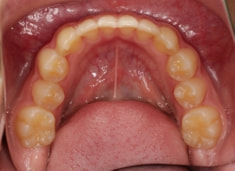

治療前

治療開始時